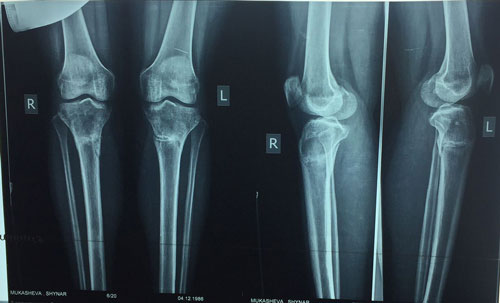

Рентген в 1,5 месяца после снятия аппаратов.

Вложения

IMG-20170522-WA0037.jpg